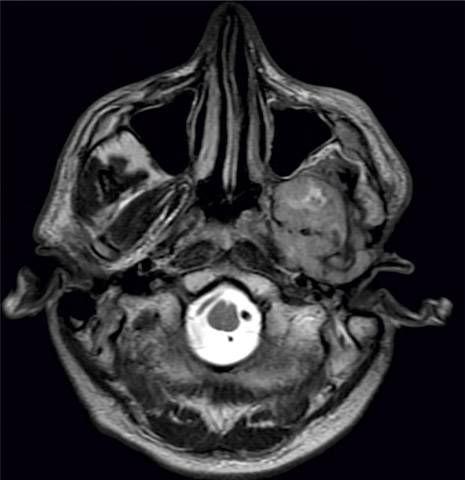

Különleges koponyasebészeti eljárást végeznek a Pécsi Tudományegyetem Klinikai Központban. Rendkívül bonyolult, oldalsó-koponyaalapi műtéteket végeznek a PTE KK fül-orr-gégészei és idegsebészei. A speciális eljárás Magyarországon jelenleg csak itt érhető el rendszeresen az érintett páciensek számára – tudatták sajtósaik.

Összetett speciális műtéteket végeznek a Pécsi Tudományegyetem Klinikai Központ Fül-Orr-Gégészeti és Fej-Nyaksebészeti Klinika, valamint az Idegsebészeti Klinika szakemberei az oldalsó koponyaalapi elváltozások kezelésében. A területen végzett műtétek hatalmas kihívás elé állítják az orvosokat, hiszen a beavatkozásokhoz komoly szakmai tapasztalatra és felkészültségre van szükség.

A kooperáció a fül és a halántékcsont jó-, és rosszindulatú elváltozásait, valamint a kisagy-híd szögleti daganatok különböző típusait kezeli a nemzetközi irányelvek szerint sebészeti és konzervatív módokon. Több alkalommal a műtét során hallásrehabilitációt is elvégzett a team egy különleges eszköz beültetésével, úgy nevezett cochlearis-implantációval.

A sikeres ellátáshoz nélkülözhetetlen személyi és tárgyi feltételek eddig csak korlátozottan, vagy egyáltalán nem voltak elérhetők Magyarországon. 2023 januárjától azonban a Pécsi Tudományegyetem Klinikai Központja biztosítja a szakmai stáb rendszeres együttműködését. Eddig 37 sikeres beavatkozást végzett el a munkacsoport. Ezekre a nagyműtétekre jelenleg kéthetente kerül sor – a betegség típusától függően az együttműködésben részt vevő klinikák valamelyikén. A Klinikai Központban a komplex műtéti beavatkozás biztonságához sokszor nélkülözhetetlen többcsatornás idegmonitor és navigációs berendezés is rendelkezésre áll, továbbá a műtéti vérzést csökkentő előzetes ún. endovascularis beavatkozásokat is elvégezhetik.